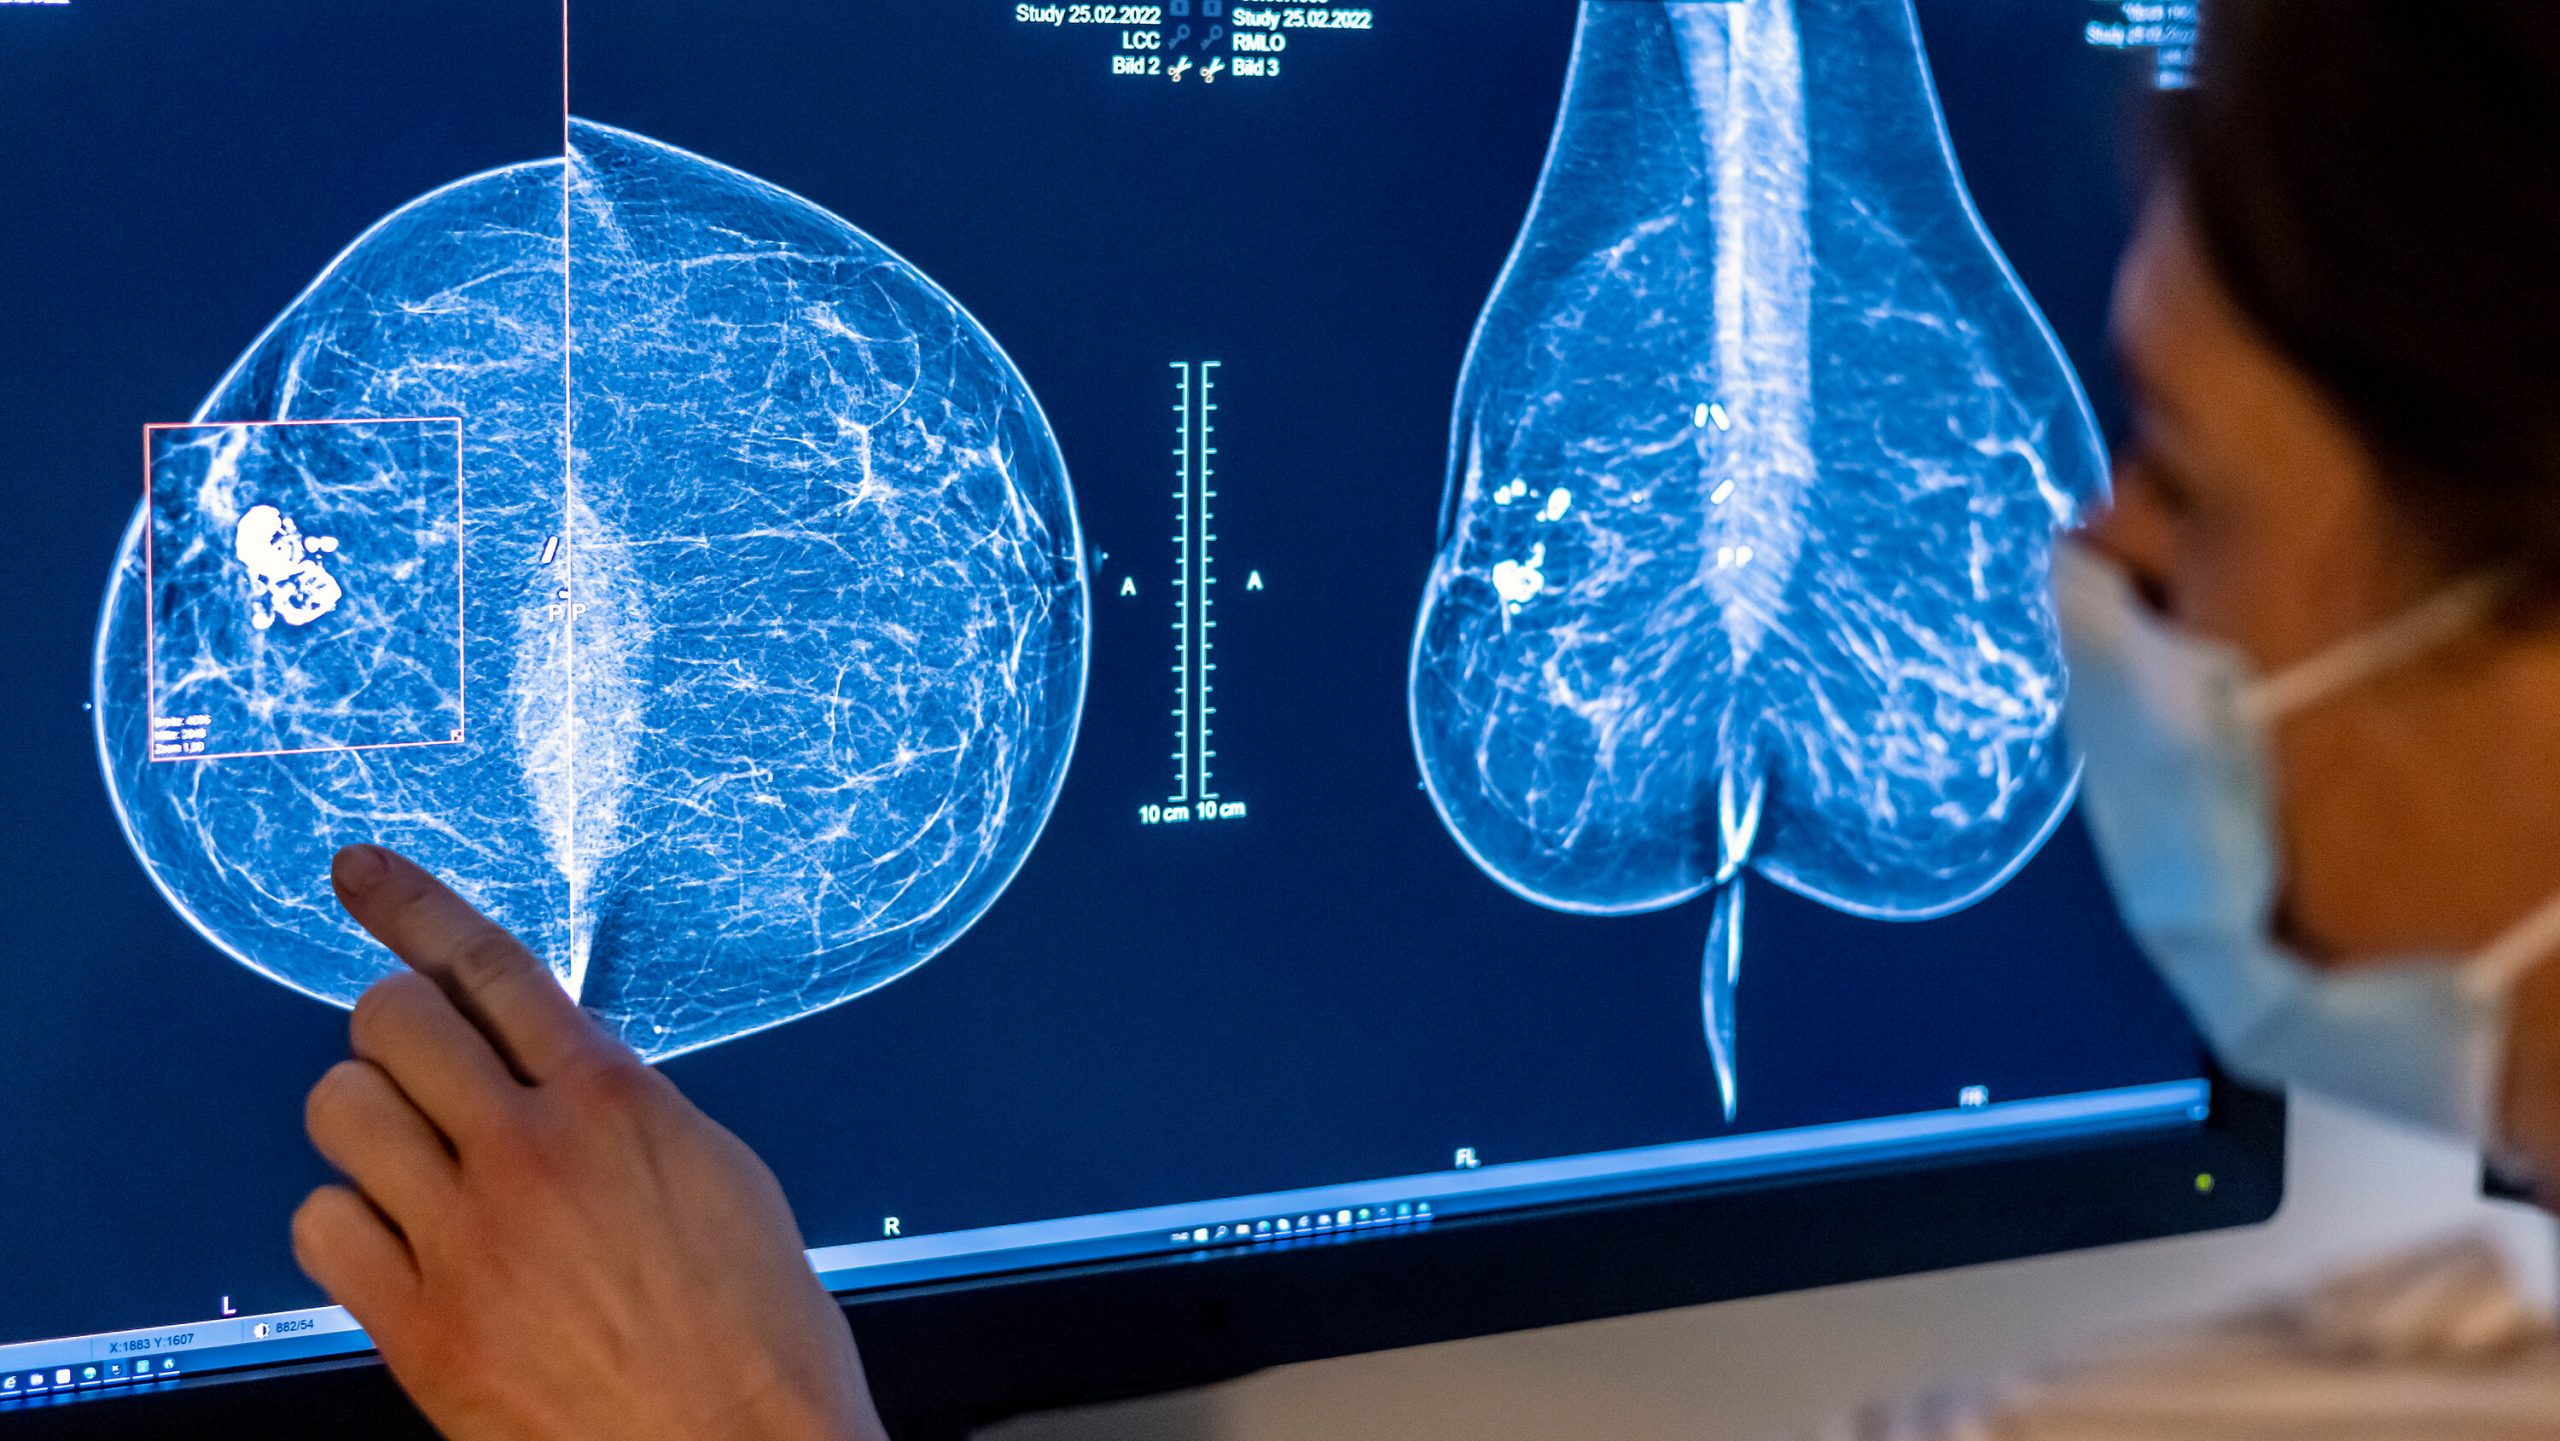

(كش بريس/وكالات) ـ أظهرت دراسة حديثة أن بإمكان الذكاء الاصطناعي تحديد النساء الأكثر عرضة لخطر الإصابة بسرطان الثدي قبل سنوات من اكتشافها لديهنّ بالفعل، وفق ما أعلن المعهد النروجي للصحة العامة الثلاثاء.

واستخدم خمسة باحثين من المعهد وجامعتي واشنطن وكاليفورنيا خوارزمية الذكاء الاصطناعي المتاحة تجاريا لتحليل صور الثدي بالأشعة السينية لـ 116495 امرأة شاركن في برنامج الفحص في النروج بين عامي 2004 و2018.

ومن بين هؤلاء، أصيبت 1607 بسرطان الثدي.

وباستخدام نظام وضع علامات للمخاطر بالاعتماد على صور الثدي بالأشعة السينية، تمكنت الخوارزمية من التنبؤ بخطر أعلى للإصابة بسرطان الثدي، وحتى تحديد الثدي المعرض للخطر، قبل أربع إلى ست سنوات من التشخيص.

وقالت المسؤولة عن المشروع ومديرة برنامج الفحص سولفيغ هوففيند في بيان “لقد وجدنا أن الذكاء الاصطناعي وضع للثدي الذي أصيب بالسرطان علامة أعلى بنحو مرتين من الثدي الآخر”.

وأضافت أن “الدراسة بيّنت أن خوارزميات الذكاء الاصطناعي المتاحة راهنا في السوق يمكن استخدامها لتطوير برامج فحص مشخصنة”.

واعتبر المعهد النروجي أن من شأن استخدام الذكاء الاصطناعي تحقيق منافع تتمثل في تحسين الكشف المبكر وخفض التكاليف واستهداف الفئات السكانية المعرضة للخطر بشكل أفضل.